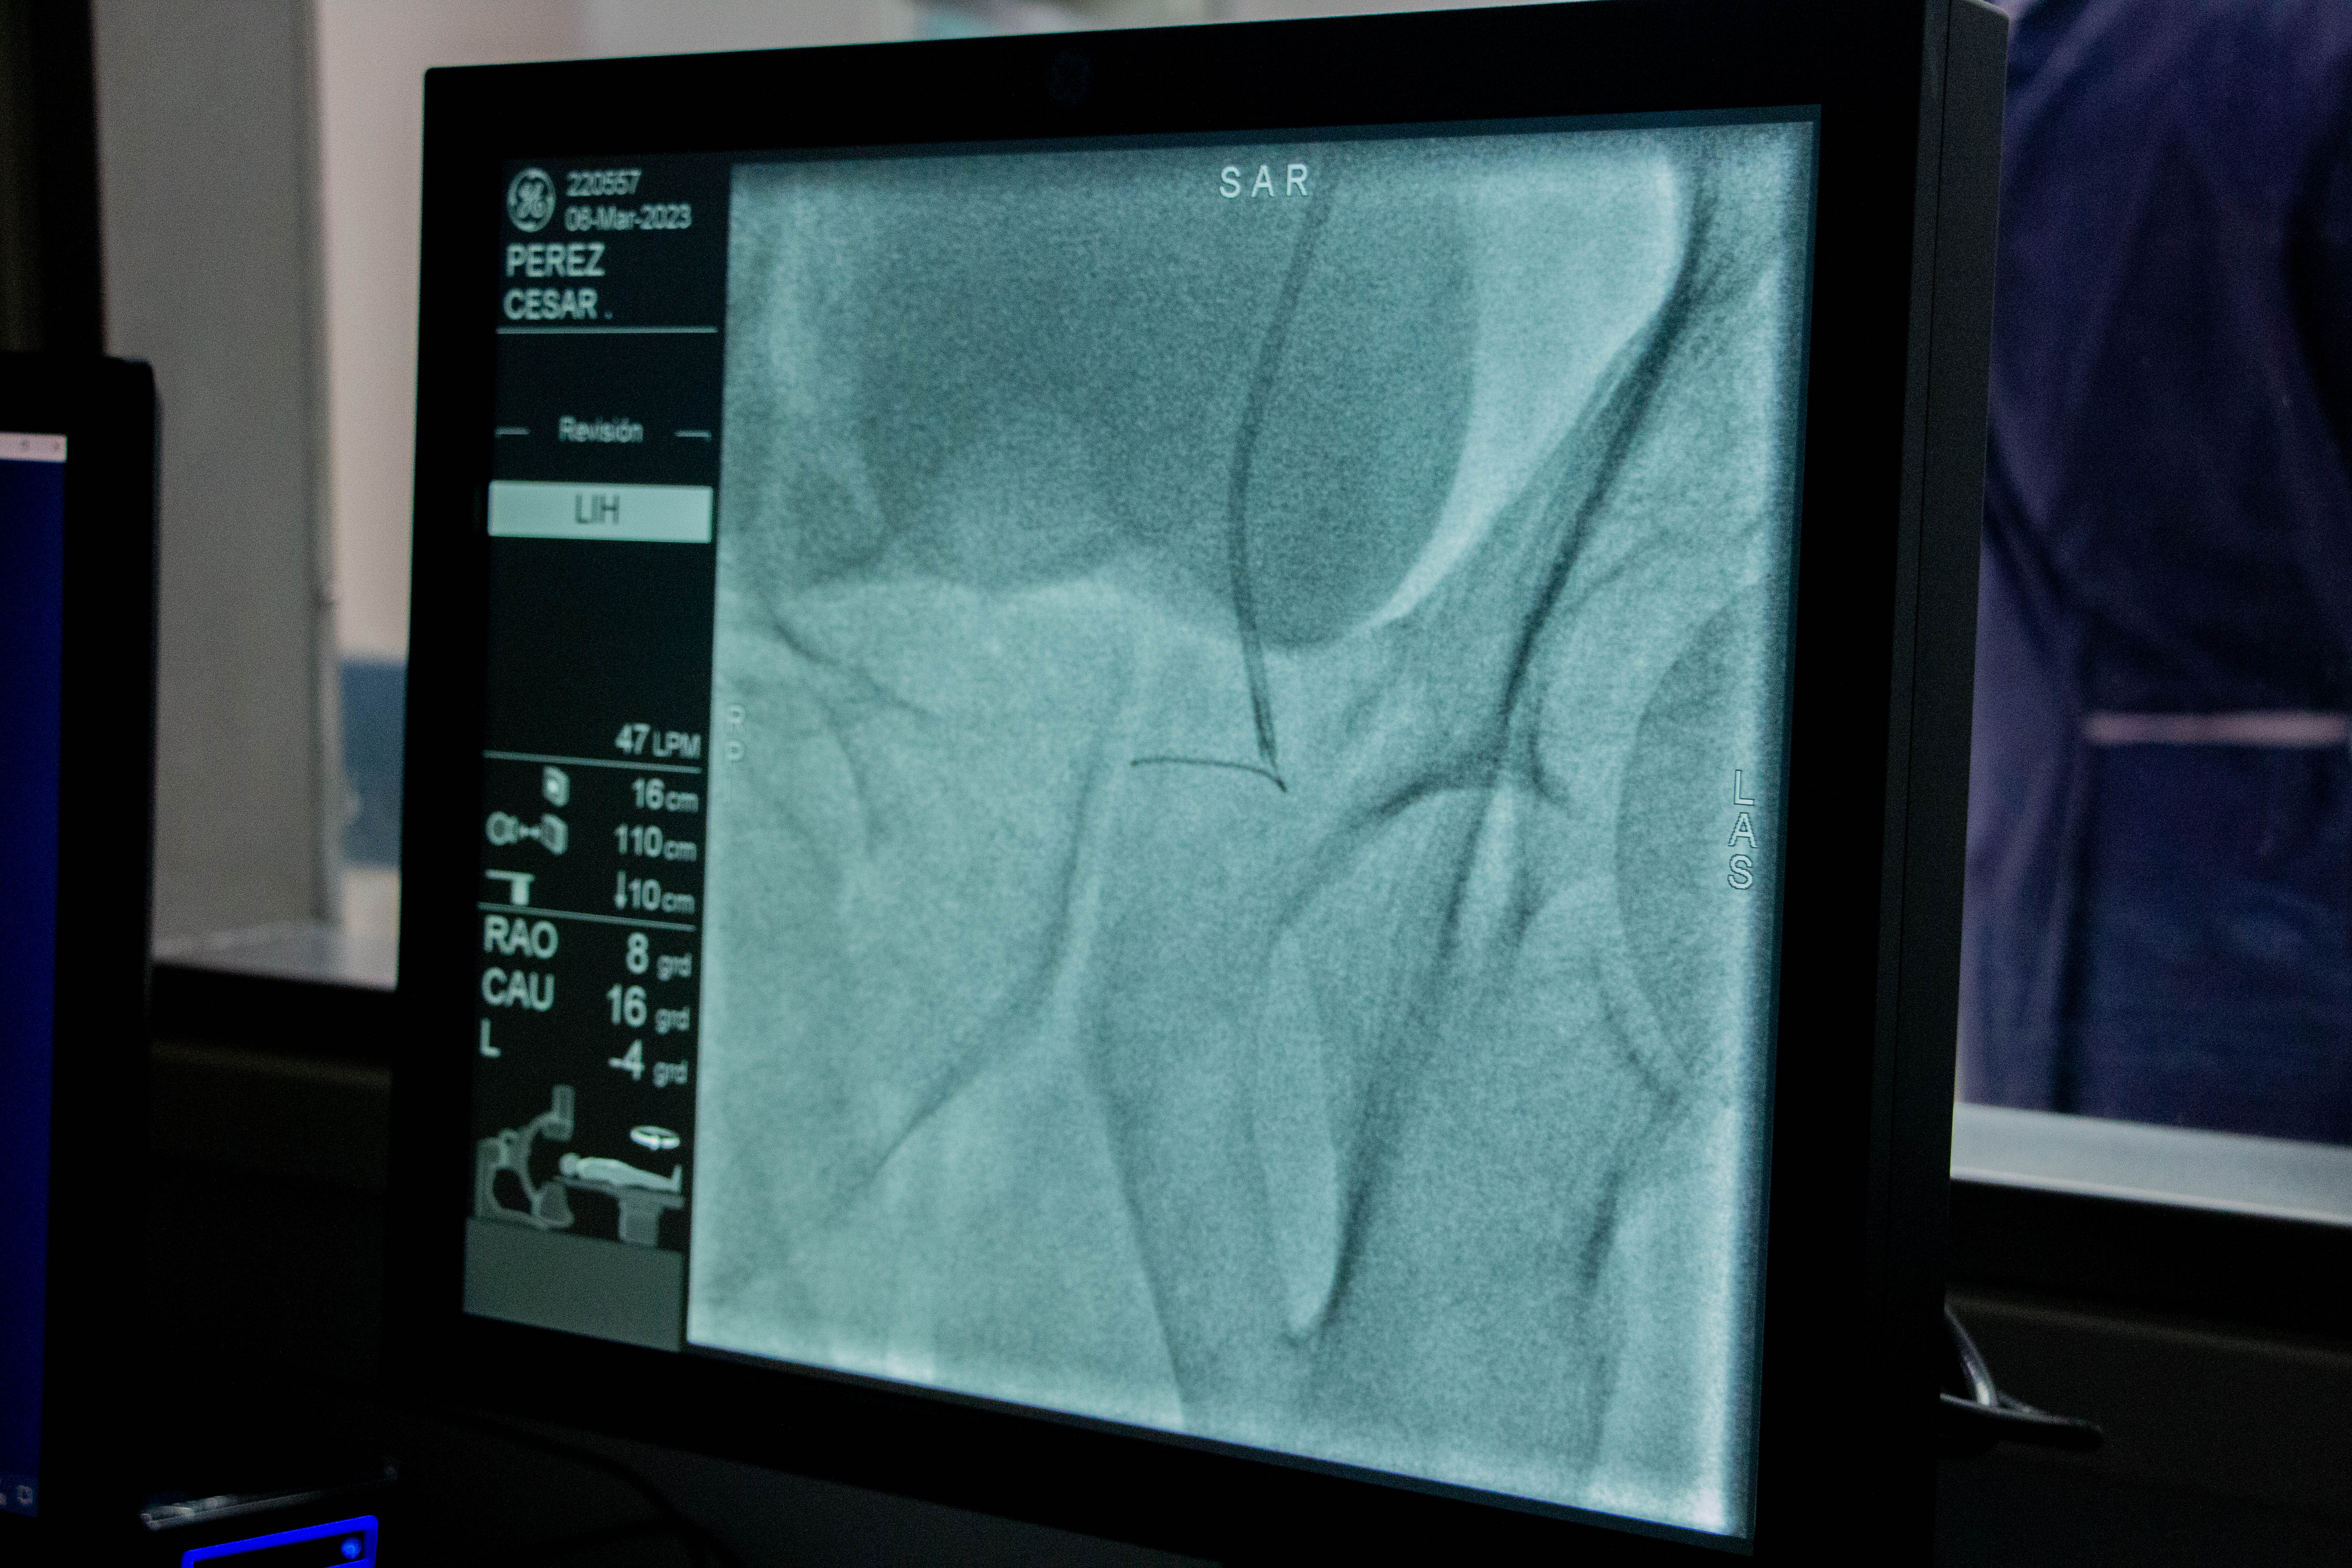

EMBOLIZACIÓN DE

ARTERIAS PROSTÁTICAS